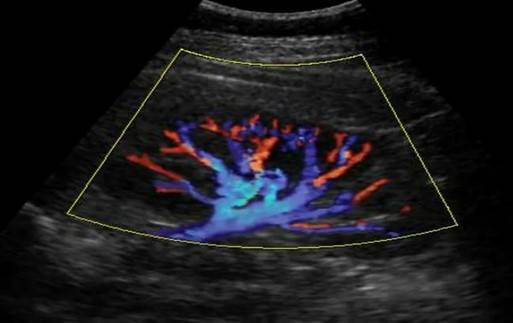

Сосуды почки, ЦДК

- Цветовое допплеровское картировании – на черно-белые анатомические структуры, полученные в результате традиционной ультрасонографии, накладывается цветное изображение, отражающее направление и скорость потока крови. Сонограммы лоцируют дефекты наполнения, области завихрений, отсутствие/усиление васкуляризации.